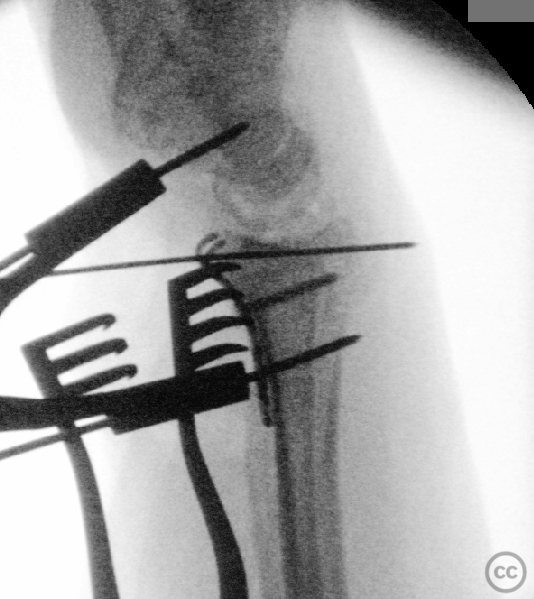

Anatomical surgical approach:  A longitudinal incision was made over the flexor carpi radialis (FCR), zigzagging over the wrist crease. Subcutaneous dissection and incision of the FCR tendon sheath were performed, followed by transection of musculus pronator quadratus fibers along the radial border of the distal FCR. The FCR tendon was retracted ulnarly, and the antebrachial fascia incised. Musculus flexor pollicis longus was identified and retracted ulnarly. The pronator quadratus was incised along its radial border and the watershed line, then elevated subperiosteally to expose the distal radius. Extended distal release of the FCR allowed wide exposure of the ulnar aspect of the lunate facet and volar lip. The flipped volar ulnar fragment was de-rotated and provisionally fixed with a Kirschner wire. Ligamentotaxis for radial styloid reduction was achieved using Kirschner wires in the scaphoid and distal radius, with a wire spreader applied for distraction. Provisional fixation was achieved with multiple Kirschner wires. A mini-fragment T-plate, cut and shaped as a hook plate, was applied to the volar ulnar lip fragment, fixed with bicortical screws, and used to engage dorsal fragments. The radial styloid was addressed with a contoured T-plate, similarly fixed with bicortical locking screws. Final multiplanar fluoroscopy confirmed anatomical reduction and hardware placement.

The flipped volar ulnar articular margin fragment was irreducible by closed means due to capsular attachment and required direct open de-rotation and fixation. The impaction and proximal displacement of the radial styloid fragments were challenging due to persistent traction from musculus brachioradialis and scaphoid pressure; ligamentotaxis using Kirschner wire spreader over the scaphoid facilitated reduction. Fragment-specific fixation was necessary: a custom-shaped hook plate for the volar ulnar lip fragment provided stable fixation and prevented dorsal instability, while a separate T-plate addressed the radial styloid. Bicortical locking screws were used to secure both plates, with some screws engaging dorsal fragments from the volar side. Careful adaptation of pronator quadratus over hardware minimized risk of musculus flexor pollicis longus irritation. Additional suture stabilization of radiocarpal ligaments to pronator quadratus provided secondary ligamnetal support.

Orthopaedic implants used:   - 1.0 mm Kirschner wire (provisional fixation) - 1.8 mm Kirschner wire (scaphoid traction) - 2.0 mm Stryker mini fragment T-plate (cut/shaped as hook plate) - 2.4 mm T-plate (radial styloid fixation)